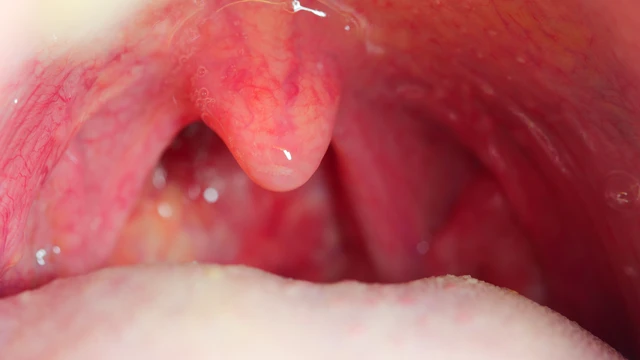

Viêm họng hạt là một căn bệnh phổ biến nhưng thường bị bỏ qua, đặc biệt là khi người bệnh chưa nhận diện được các dấu hiệu ban đầu. Trong bài viết này, chúng ta sẽ cùng tìm hiểu về hình ảnh viêm họng hạt qua các giai đoạn khác nhau, giúp bạn dễ dàng nhận diện và phân biệt bệnh.

Viêm họng hạt là bệnh lý dễ gặp nhất là trong thời điểm giao mùa, khí hậu thay đổi. Bệnh dễ nhận biết và có thể điều trị dứt điểm. Biết được hình ảnh viêm họng hạt ở cuống lưỡi sẽ giúp bạn dễ nhận biết tình trạng bệnh, từ đó có phương pháp điều trị phù hợp.